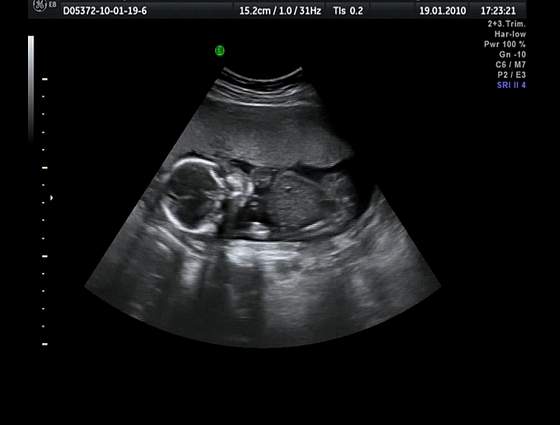

A poniżej przedstawiam moją "bardziej" Jagusię niż Kazika ;-) w 19 tygodniu jej życia: